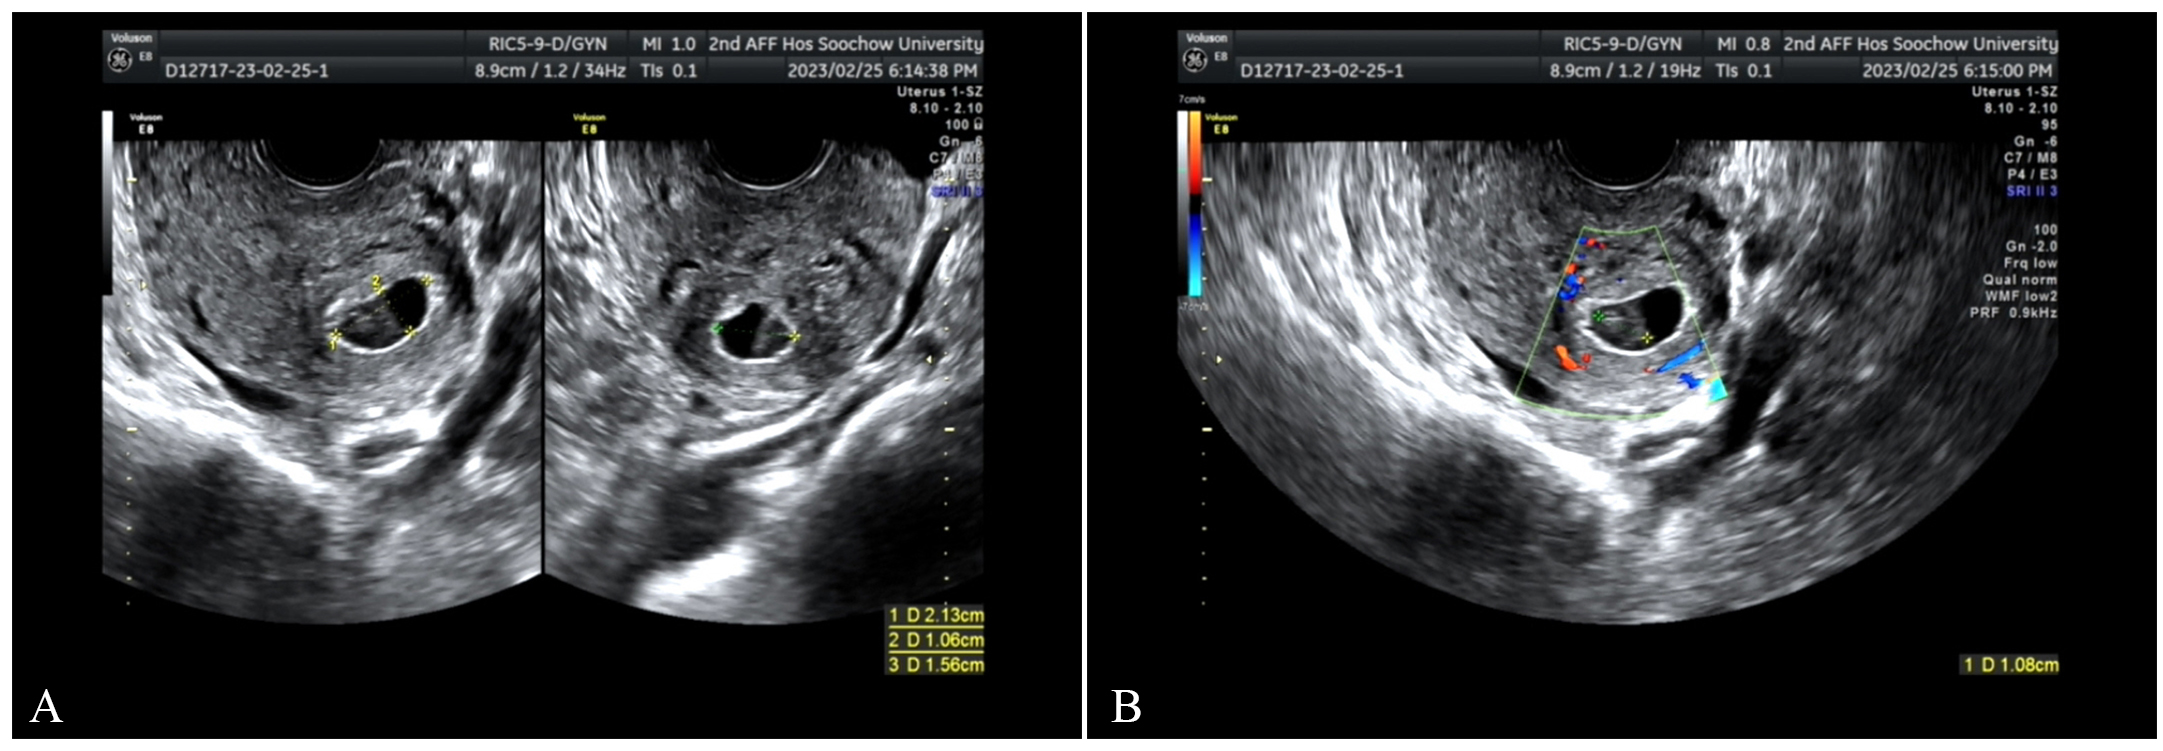

On February 26, transvaginal ultrasound scan. (A) A gestational sac

was seen near the uterine angle, measuring approximately 21 mm

On February 28, transvaginal three-dimensional ultrasound (TDU). (A) There was an echo of the gestational sac between the muscle walls. (B) Blood flow signals around it are increased.